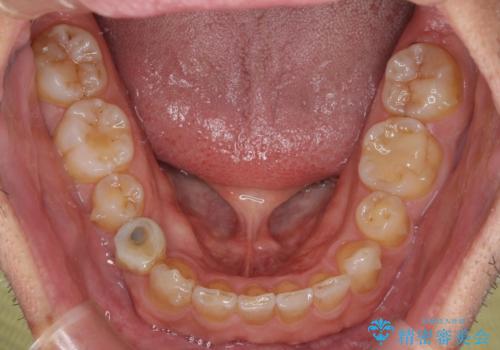

- 上下前歯のデコボコと下顎小臼歯の欠損によるスペースを気にして来院された患者様です。

下顎は左右1本ずつ小臼歯が欠損しており、右側にはやや大きな欠損がありました。

欠損により下顎歯列は相対的に小さく、上顎に深く咬みこんでしまうディープバイトとなっていました。

インビザラインによる治療を希望されたため、左側のスペースは閉じ、右側はスペースをより拡大し、インプラント補綴を行うこととしました。

咬合力が強く、インビザラインのみではディープバイトを改善することができず、半年間ほどワイヤー装置による矯正治療を行いました。

インプラントの埋入は矯正治療中に行い、矯正治療後はインプラント上補綴および、前歯のセラミック治療を行いました。